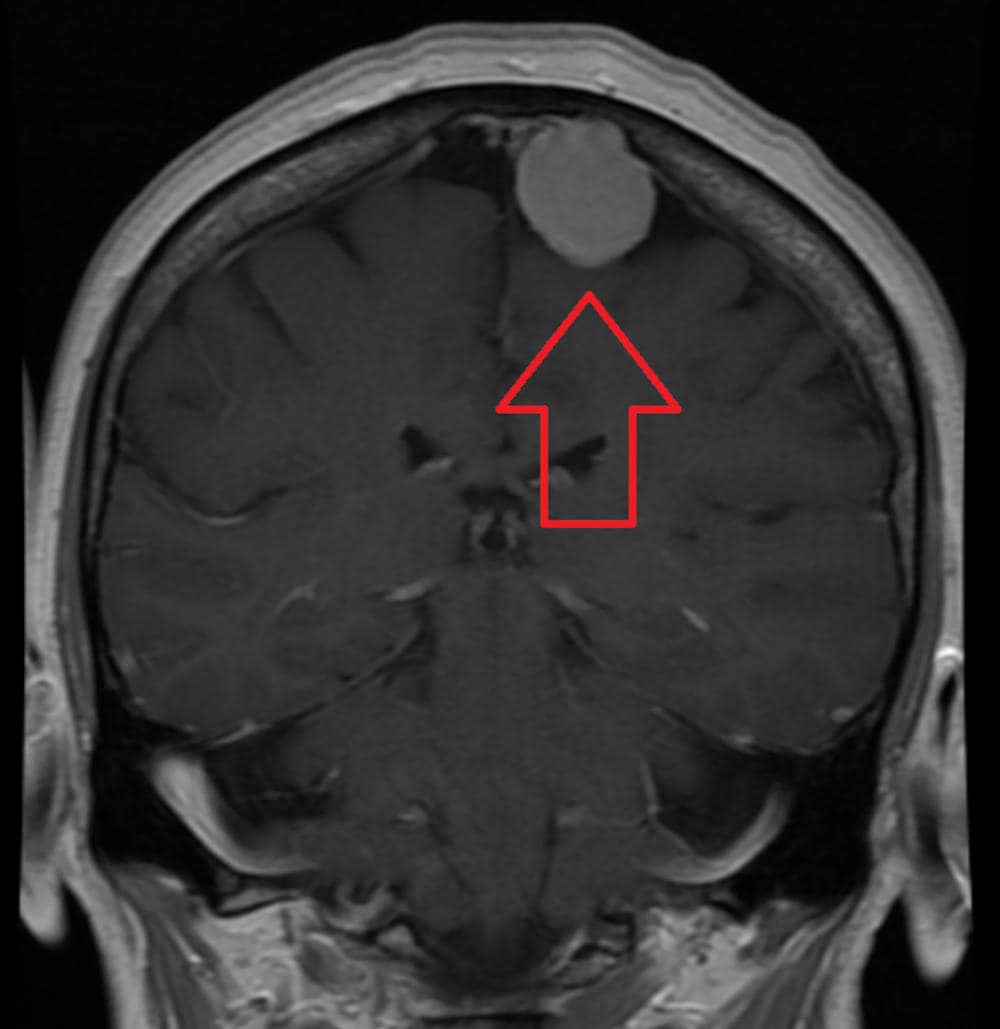

Una diagnosi di tumore al cervello è spesso un fulmine a ciel sereno, un colpo capace di causare una comprensibile ansia e preoccupazione in chiunque, ma in pochi sanno che il meningioma è il tumore cerebrale più comune, rendendo conto di circa un caso su tre, e nella maggior parte dei casi è benigno.

Di norma un meningioma cresce lentamente, spesso senza segni e sintomi significativi ed anche per questo non sempre richiedono un trattamento immediato, ma semplicemente un periodico controllo nel tempo.

Tipicamente la diagnosi viene posta grazie all’esecuzione di esami avanzati di imaging, quali TAC e risonanza magnetica.

By James Heilman, MD – Own work, CC BY-SA 4.0, https://commons.wikimedia.org/w/index.php?curid=47816877